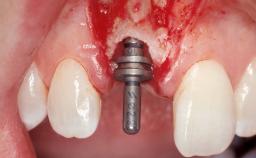

Late Placement of an Implant in a Maxillary Left Central Incisor Site

Type of Implants Two-Piece

Placement Protocol Early or late implant placement

Bone Volume Deficient horizontally, requiring prior grafting